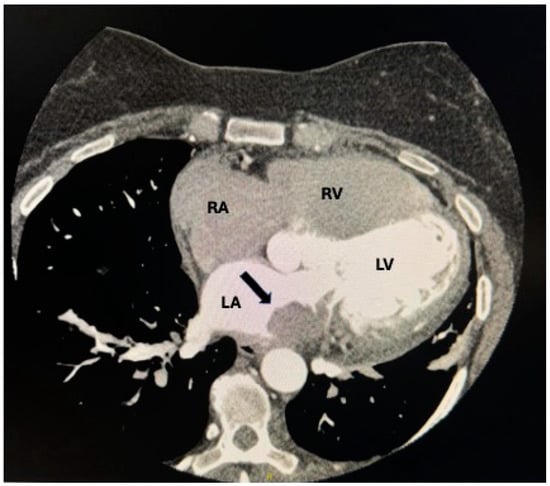

- Aggeli, C.; Dimitroglou, Y.; Raftopoulos, L.; Sarri, G.; Mavrogeni, S.; Wong, J.; Tsiamis, E.; Tsioufis, C. Cardiac Masses: The Role of Cardiovascular Imaging in the Differential Diagnosis. Diagnostics 2020, 10, 1088. (In English) [Google Scholar] [CrossRef] [PubMed]

- Li, X.; Chen, Y.; Liu, J.; Xu, L.; Li, Y.; Liu, D.; Sun, Z.; Wen, Z. Cardiac magnetic resonance imaging of primary cardiac tumors. Quant. Imaging Med. Surg. 2020, 10, 294–313. (In English) [Google Scholar] [CrossRef] [PubMed]